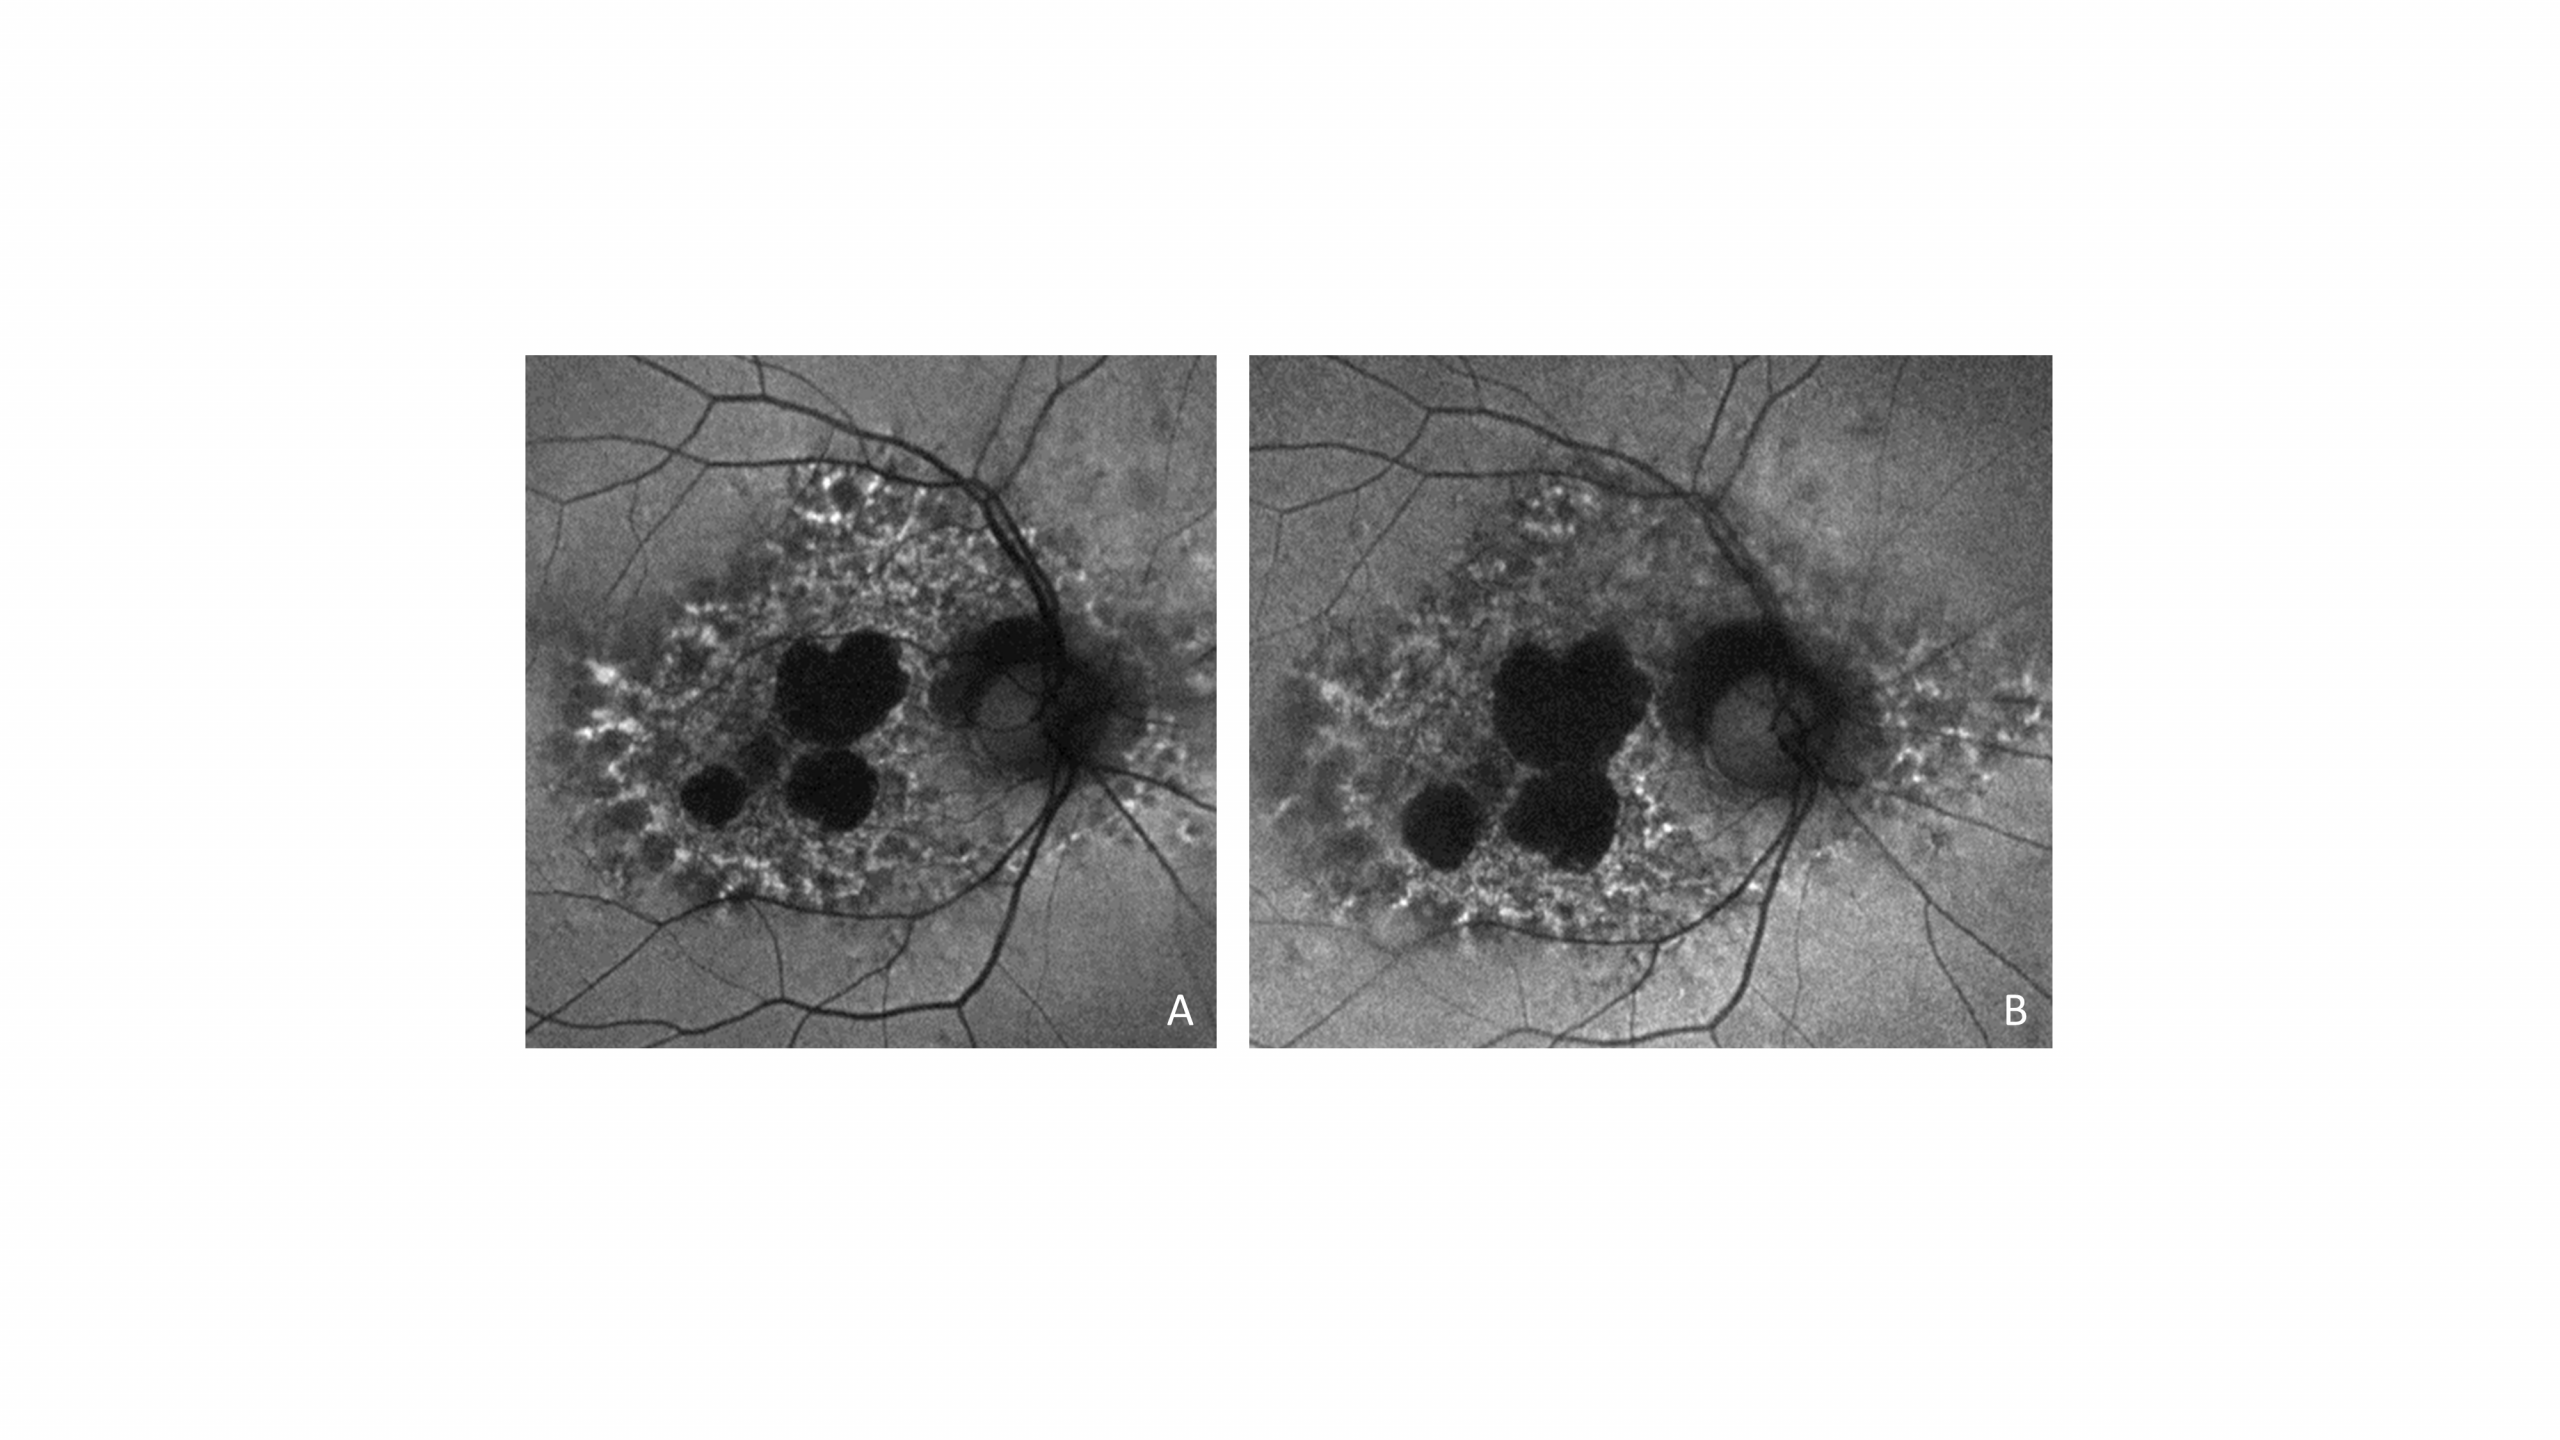

Fundus autofluorescence images of a pentosan polysulfate maculopathy patient with progressive atrophy at four (A) and eighteen (B) months after pentosan polysulfate cessation.

| current | 12:14, January 22, 2021 | 4,000 × 2,250 (2.68 MB) | Nieraj.Jain (talk | contribs) | Fundus autofluorescence images of a pentosan polysulfate maculopathy patient with progressive atrophy at four (A) and eighteen (B) months after pentosan polysulfate cessation. Reprinted with permission from the American Medical Association from: Shah R... | |